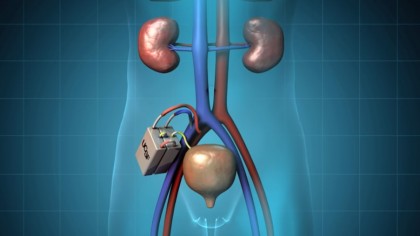

Cercetătorii de la Universitatea San Francisco au demonstrat că celulele renale pot fi implementate la un animal fără imunosupresie, dar și că acestea își pot îndeplini funcția pe o perioadă extinsă. În cadrul conferinței de la Washington, oamenii de știință de la Societatea Americană de Nefrologie au anunțat că rinichiul artificial intră într-o nouă etapă, ce urmează să se finalizeze printr-un studiu clinic efectuat pe subiecți umani.

Cercetătorii de la Universitatea San Francisco au reușit să implementeze cu succes un prototip bioreactor renal care conține celule renale umane la porci, fără a fi semnalate probleme de siguranță. Dispozitivul nu a declanșat o reacție imună și nici nu a provocat cheaguri de sânge la animale. Studiul oamenilor de știință demonstrează că există posibilitatea implementării celulelor renale la animale fără imunosupresie. Folosindu-se de rezultatele actualei anchete, cercetătorii se vor putea concentra în viitor pe extinderea bioreactorului și pe combinarea acestuia cu componenta de filtrare a sângelui din rinichiul artificial, astfel încât organul artificial să poată fi folosit pentru dializă.

Foto: University of California San Francisco, The Kidney Project